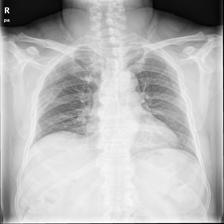

To pre-train a high-performance X-ray foundation model, the first thing we need to do is the collection of large-scale X-ray images. Therefore, a large-scale and high-resolution dataset that contains X-ray medical images is collected for the pre-training. Some representative samples are visualized in Fig. 3.